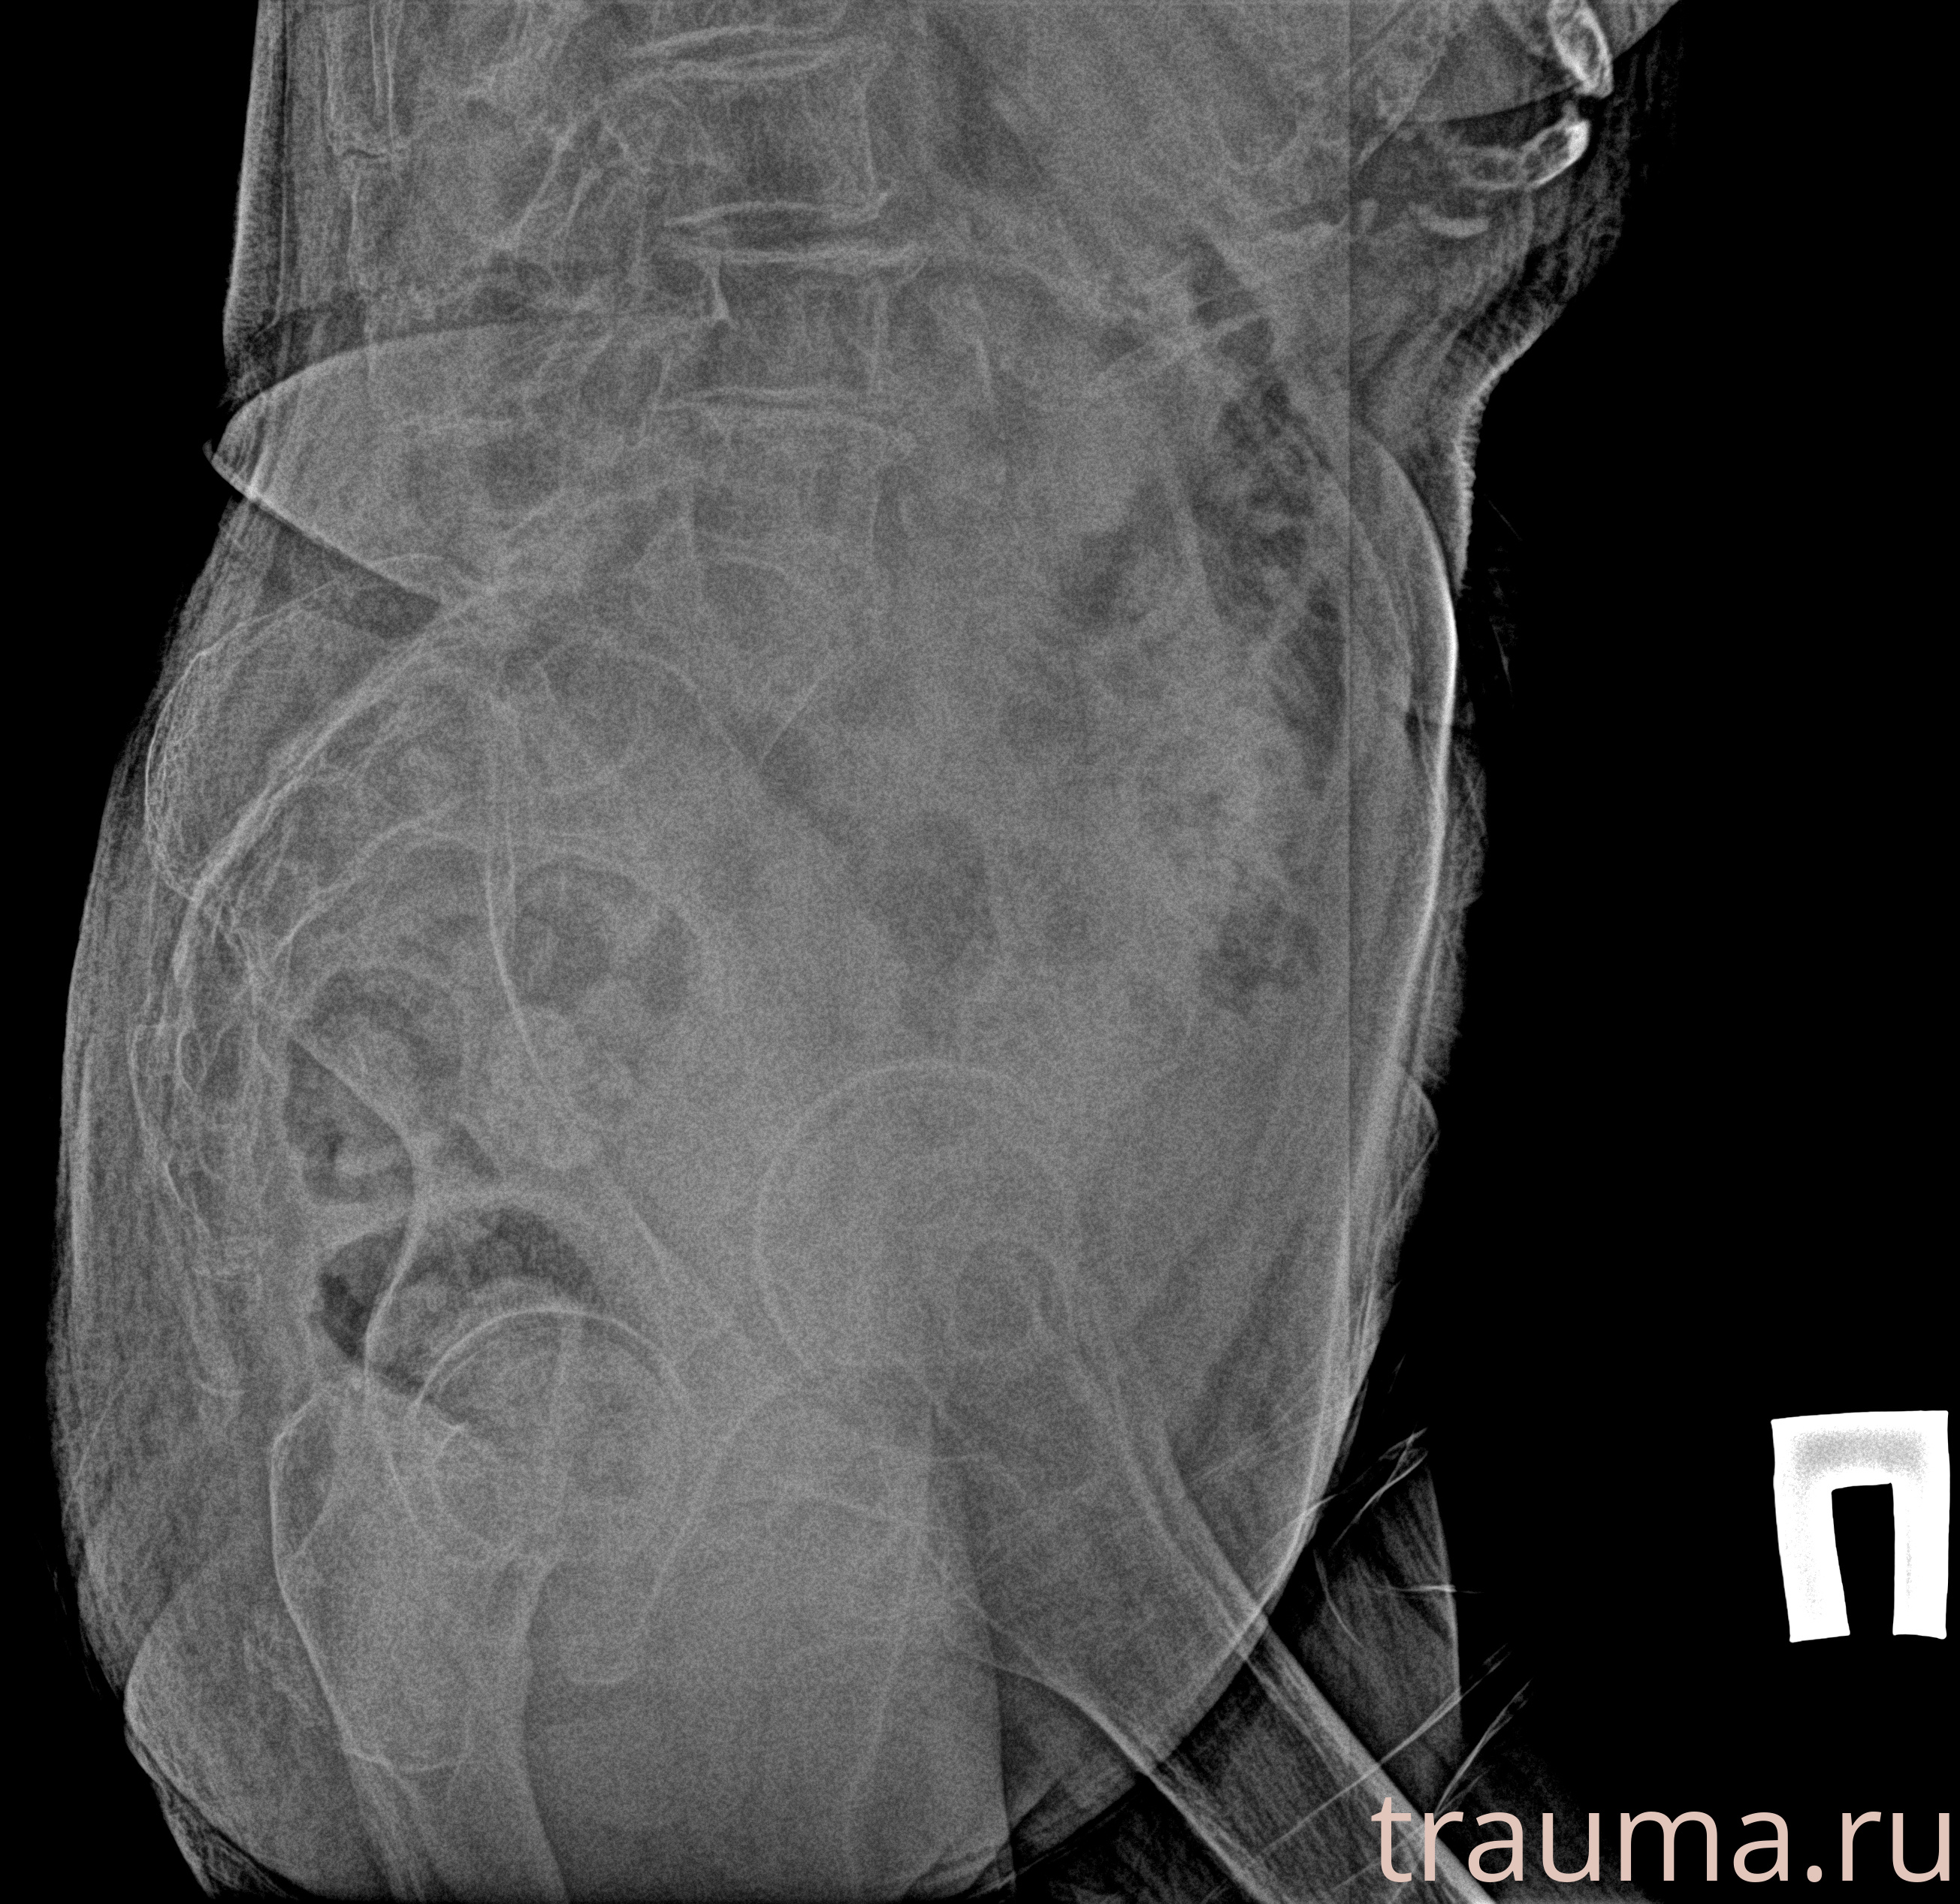

Рентген на дому: по вашему адресу приезжает врач-рентгенолог, травматолог-ортопед с мобильным рентгеновским аппаратом, проводит диагностику травмы или заболевания, делает необходимые рентгенограммы, дает рекомендации по дальнейшему лечению. Получить качественные снимки в домашних условиях возможно благодаря уникальной методике, разработанной МосРентген Центром для института  Склифосовского